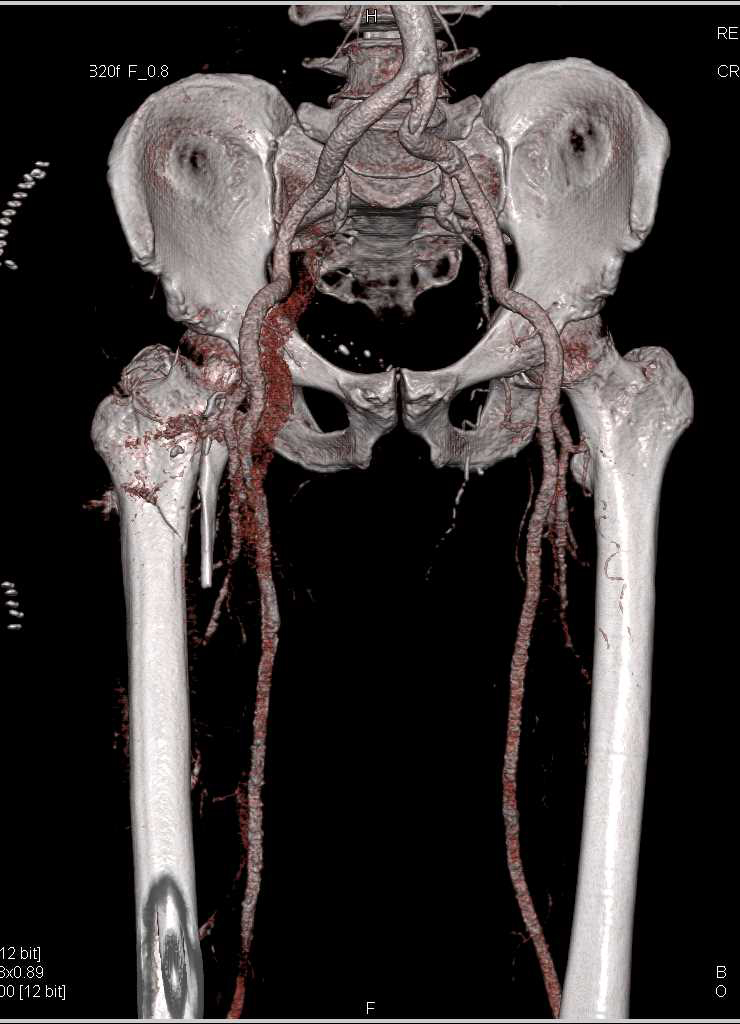

Aneurysm of the Celiac Artery